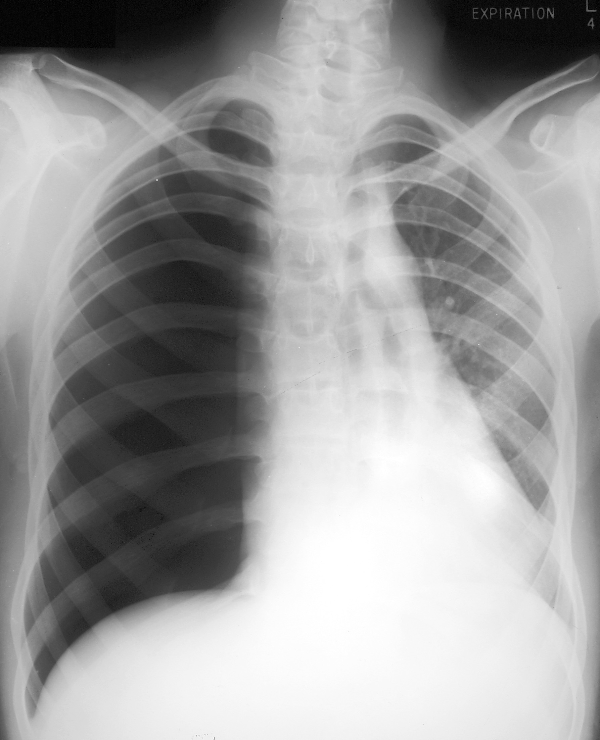

What is shown? Name 2 possible causes.

Left lung collapse/consolidation - considerable mediastinal shift to the left so there must be a considerable loss of lung volume. There is an air bronchogram of at least one of the larger bronchi indicating consolidation.

Pneumonia and obstruction of the left bronchus